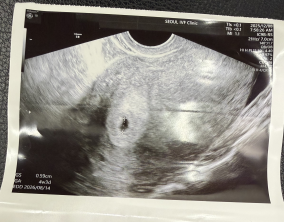

조심스러운 기쁨이 안도가 되기까지

이유정 원장님께서 차분하고 사실적으로 치료 과정과 정보를 설명해 주셔서 불안한 마음이 많이 줄어들었습니다. 미디어에서 접했던 이야기들로 걱정이 컸던 만큼, 현실적인 설명…